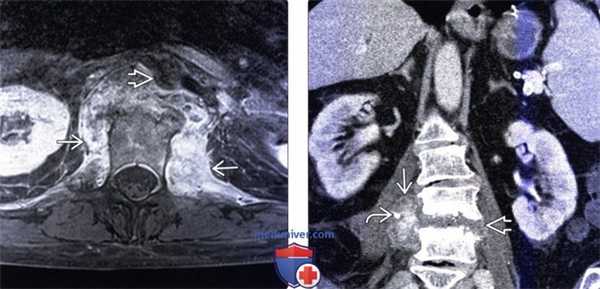

(Слева) Аксиальный срез, Т1-ВИ FS с КУ: ярко контрастирующееся гетерогенное паравертебральное жидкостное образование, окружающее переднюю и боковые поверхности тела поясничного позвонка. Накапливающие контраст ткани располагаются в непосредственной близости к аорте.

(Справа) Фронтальный КТ-срез: справа определяется паравертебральный абсцесс, сформировавшийся на фоне спондилодисцита. В полости абсцесса виден катетер. Гиперденсное внутреннее содержимое абсцесса может представлять собой продукты распада крови и гной.